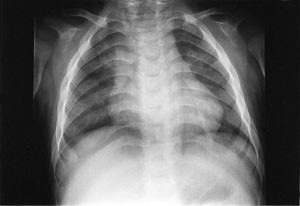

Pasienten ble så 13 måneder gammel innlagt i barneavdeling i forbindelse med ny feberepisode. Ved innleggelsen var han dystrofisk, med stor abdomen, tynne ekstremiteter og slunkne nates. Noe grove ansiktstrekk ble bemerket, men gav ikke umiddelbart videre assosiasjoner. Utredning av malabsorpsjon med tanke på cøliaki ble startet. Metabolsk screening av urin og serum ble rekvirert. Røntgen thorax viste klare lunger og et normalt stort hjerte, men påfallende brede costae (fig 1). Fysioterapeutisk vurdering bemerket en forsinket motorisk utvikling og stive ledd. Øre-nese-hals-undersøkelse viste betydelig nasalstenose og hypertrofiske tonsiller. Foreldrene kunne fortelle om uttalt pustebesvær og sterk snorking om natten, med tendens til pustestopp. Primær malabsorpsjon og cøliaki ble utelukket med serologiske prøver. Ultralyd abdomen viste leverstørrelse i øvre normalområde.

Omfattende radiologisk utredning ble rekvirert. Røntgen av kraniet viste et relativt stort nevrokranium (fig 2) med sannsynlig fortykket calvarium i basale deler. Røntgen av columna viste en kyfotisk knekk på torakolumbalovergangen (fig 3). Røntgen av bekken viste dysplastiske hofter bilateralt (fig 4). Røntgen av håndledd viste forandring av metakarpene. Røntgenologenes endelige konklusjon var dysostosis multiplex, forenlig med Hurlers syndrom. Undersøkelse hos øyelege styrket denne mistanken ytterligere, da det ble funnet bilateral, diffus tilsløring av hornhinnene. Plastisk kirurg bekreftet at det forelå triggerfinger på høyre hånds 4. finger, et typisk funn ved Hurlers syndrom.